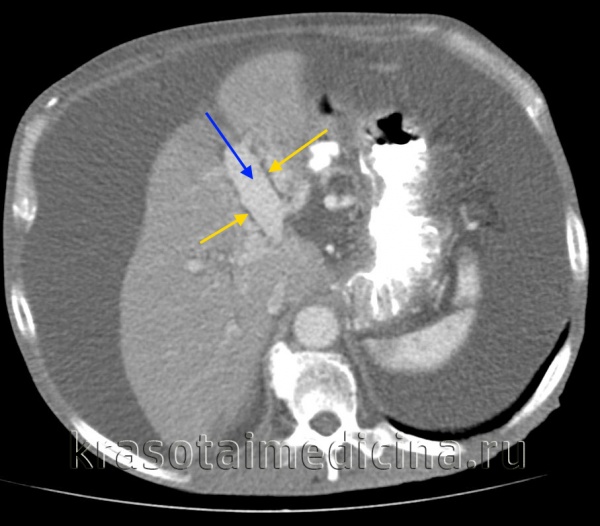

КТ ОБП. Этот же пациент, расширенный левый долевой ствол воротной вены (синяя стрелка) с периваскулярным отеком (желтая стрелка).